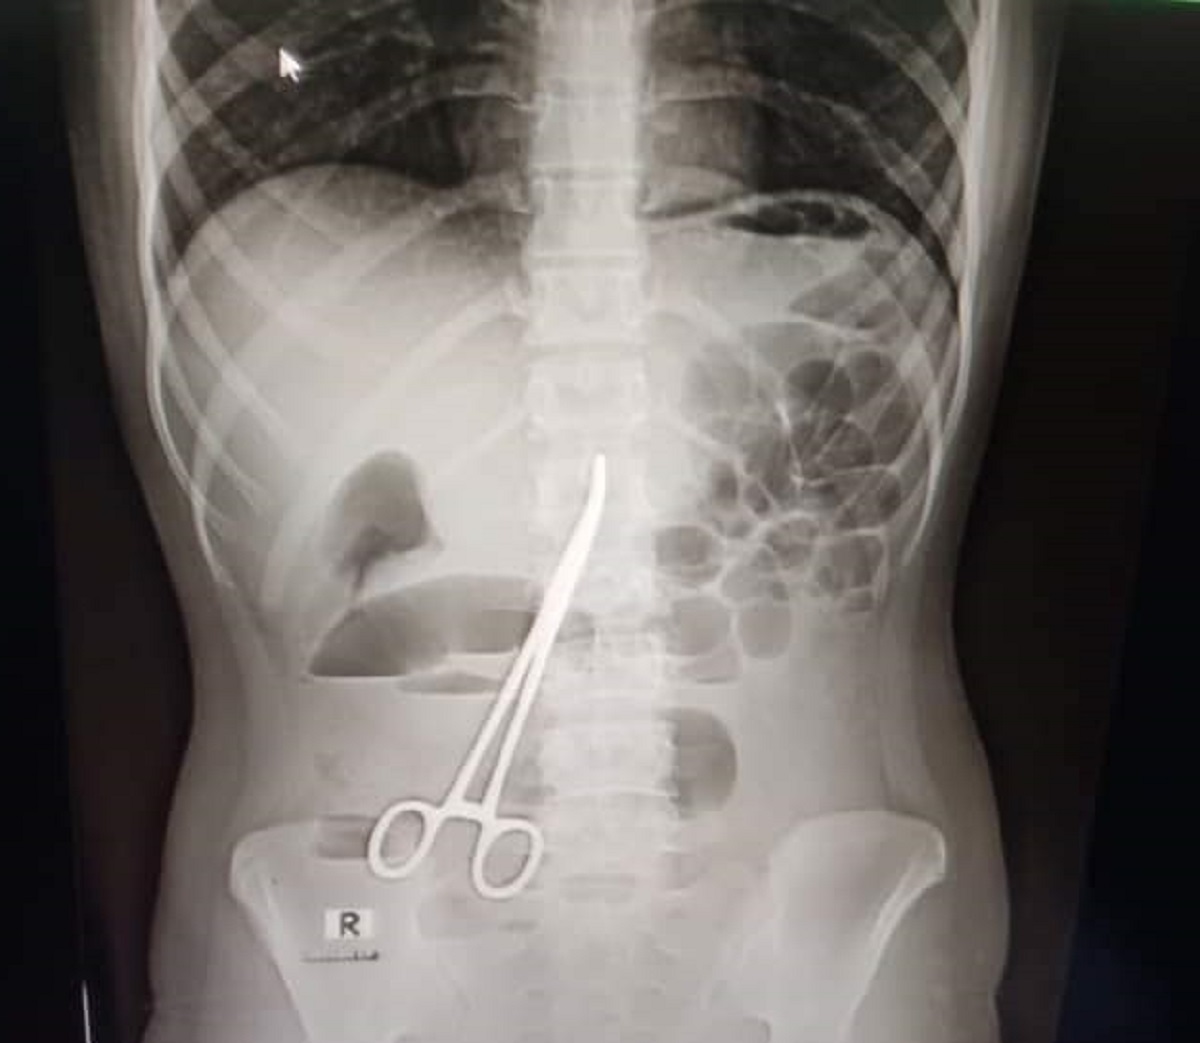

এক্সরে করার পর সেই তরুণীর পেটে কাঁচির উপস্থিতি ধরা পড়ে।

ফরিদপুর বঙ্গবন্ধু শেখ মুজিব মেডিকেল কলেজ হাসপাতালে এক তরুণীর অপারেশনের পর পেটের ভেতর কাঁচি রেখে সেলাই করে দেয়ার অভিযোগ উঠেছে। অপারেশনটি করা হয়েছিল গত বছরের মার্চে। সম্প্রতি মুকসুদপুরের এক হাসপাতালে এক্সরে করা হলে বিষয়টি ধরা পড়ে।

এরপর মনিরা অন্তঃস্বত্ত্বা হওয়ার পর বাচ্চা নষ্ট হলে তাকে বাবার বাড়িতে পাঠিয়ে দেন স্বামী। এরপরেও বিভিন্ন গ্রাম্য চিকিৎসা করানো হয়। কিন্তু তার পেট ব্যথা কমেনি। গত দু’দিন আগে পেটে অসহনীয় ব্যথা উঠলে তাকে মুকসুদপুরের একটি বেসরকারি ক্লিনিকে চিকিৎসার জন্য আনা হয়। ওই ক্লিনিকে এক্সরের মাধ্যমে চিকিৎসকরা দেখতে পান, মনিরার পেটের মধ্যে একটি ঝকঝকে কাঁচি আছে।

এ বিষয়ে মুকসুদপুর স্বাস্থ্য কমপ্লেক্সের কয়েকজন চিকিৎসক জানান, আমাদের সন্দেহ হলে তাকে একটি এক্সরে করতে বলি। পরে এক্সরে রিপোর্ট আসার পর কাঁচি দেখতে পাওয়া যায়। কয়েকজন চিকিৎসক বলছেন, গত বছরের ৩ মার্চ একটি অপারেশনের সময় ভুলে তার পেটের ভেতরে এ কাঁচিটি রেখে দেয়া হয়েছিল।

চিকিৎসকরা বলেছেন, ওই কাঁচির হাতলে সামান্য মরচে পড়ে গেছে এবং ওই যুবতীর পেটের ভেতরের অঙ্গ-প্রত্যঙ্গের সাথে জড়িয়ে গেছে এটি। দ্রুত অপারেশন করে কাঁচিটি বের করা না হলে রোগীর অবস্থা আরও খারাপ হতে পারে বলে জানান তারা।